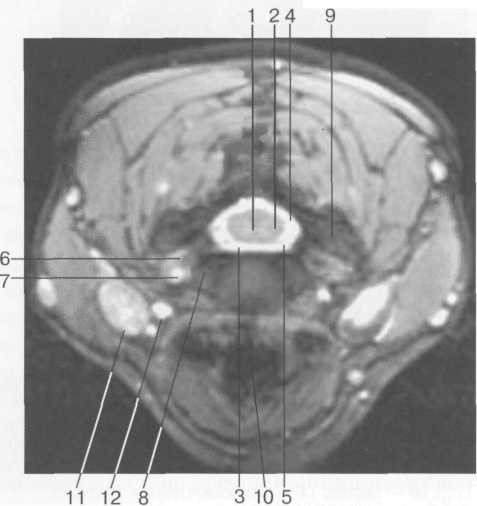

Рис. 41. МРТ. Поперечный срез на уровне межпоз­вонкового диска Clv_v. Т2-ВИ.

1 -- серое вещество спинного мозга; 2 -- белое веще­ство спинного мозга; 3 -- субарахноидальное про­странство; 4 -- задний корешок спинномозгового нерва; 5 -- передний корешок спинномозгового не­рва; 6 -- спинномозговой нерв; 7 -- позвоночная ар­терия; 8 -- крюч ко видный отросток; 9 -- фасетки суставных отростков; 10 -- трахея; 11 -- яремная вена; 12 -- сонная артерия.